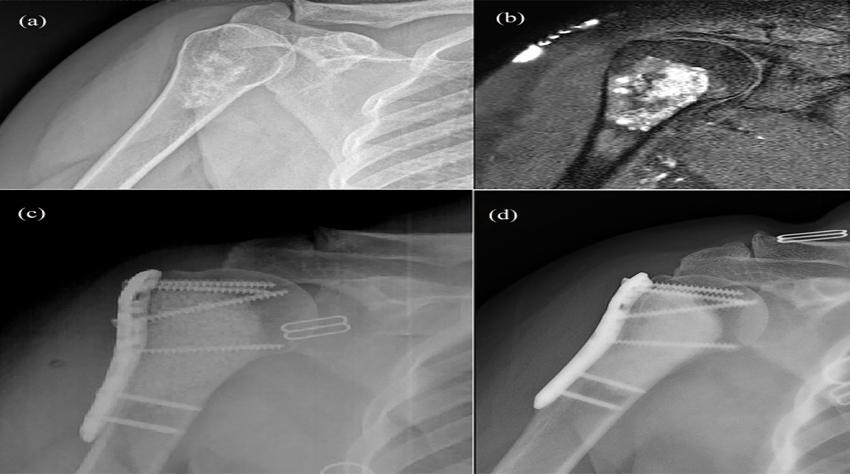

Более...IntroductionFor filling bone defects after curettage, autologous bone grafting offers osteoconductive, osteoinductive, and osteogenic properties. Döring et al [4] demonstrated that filling bone defects with autologous bone after curettage resulted...